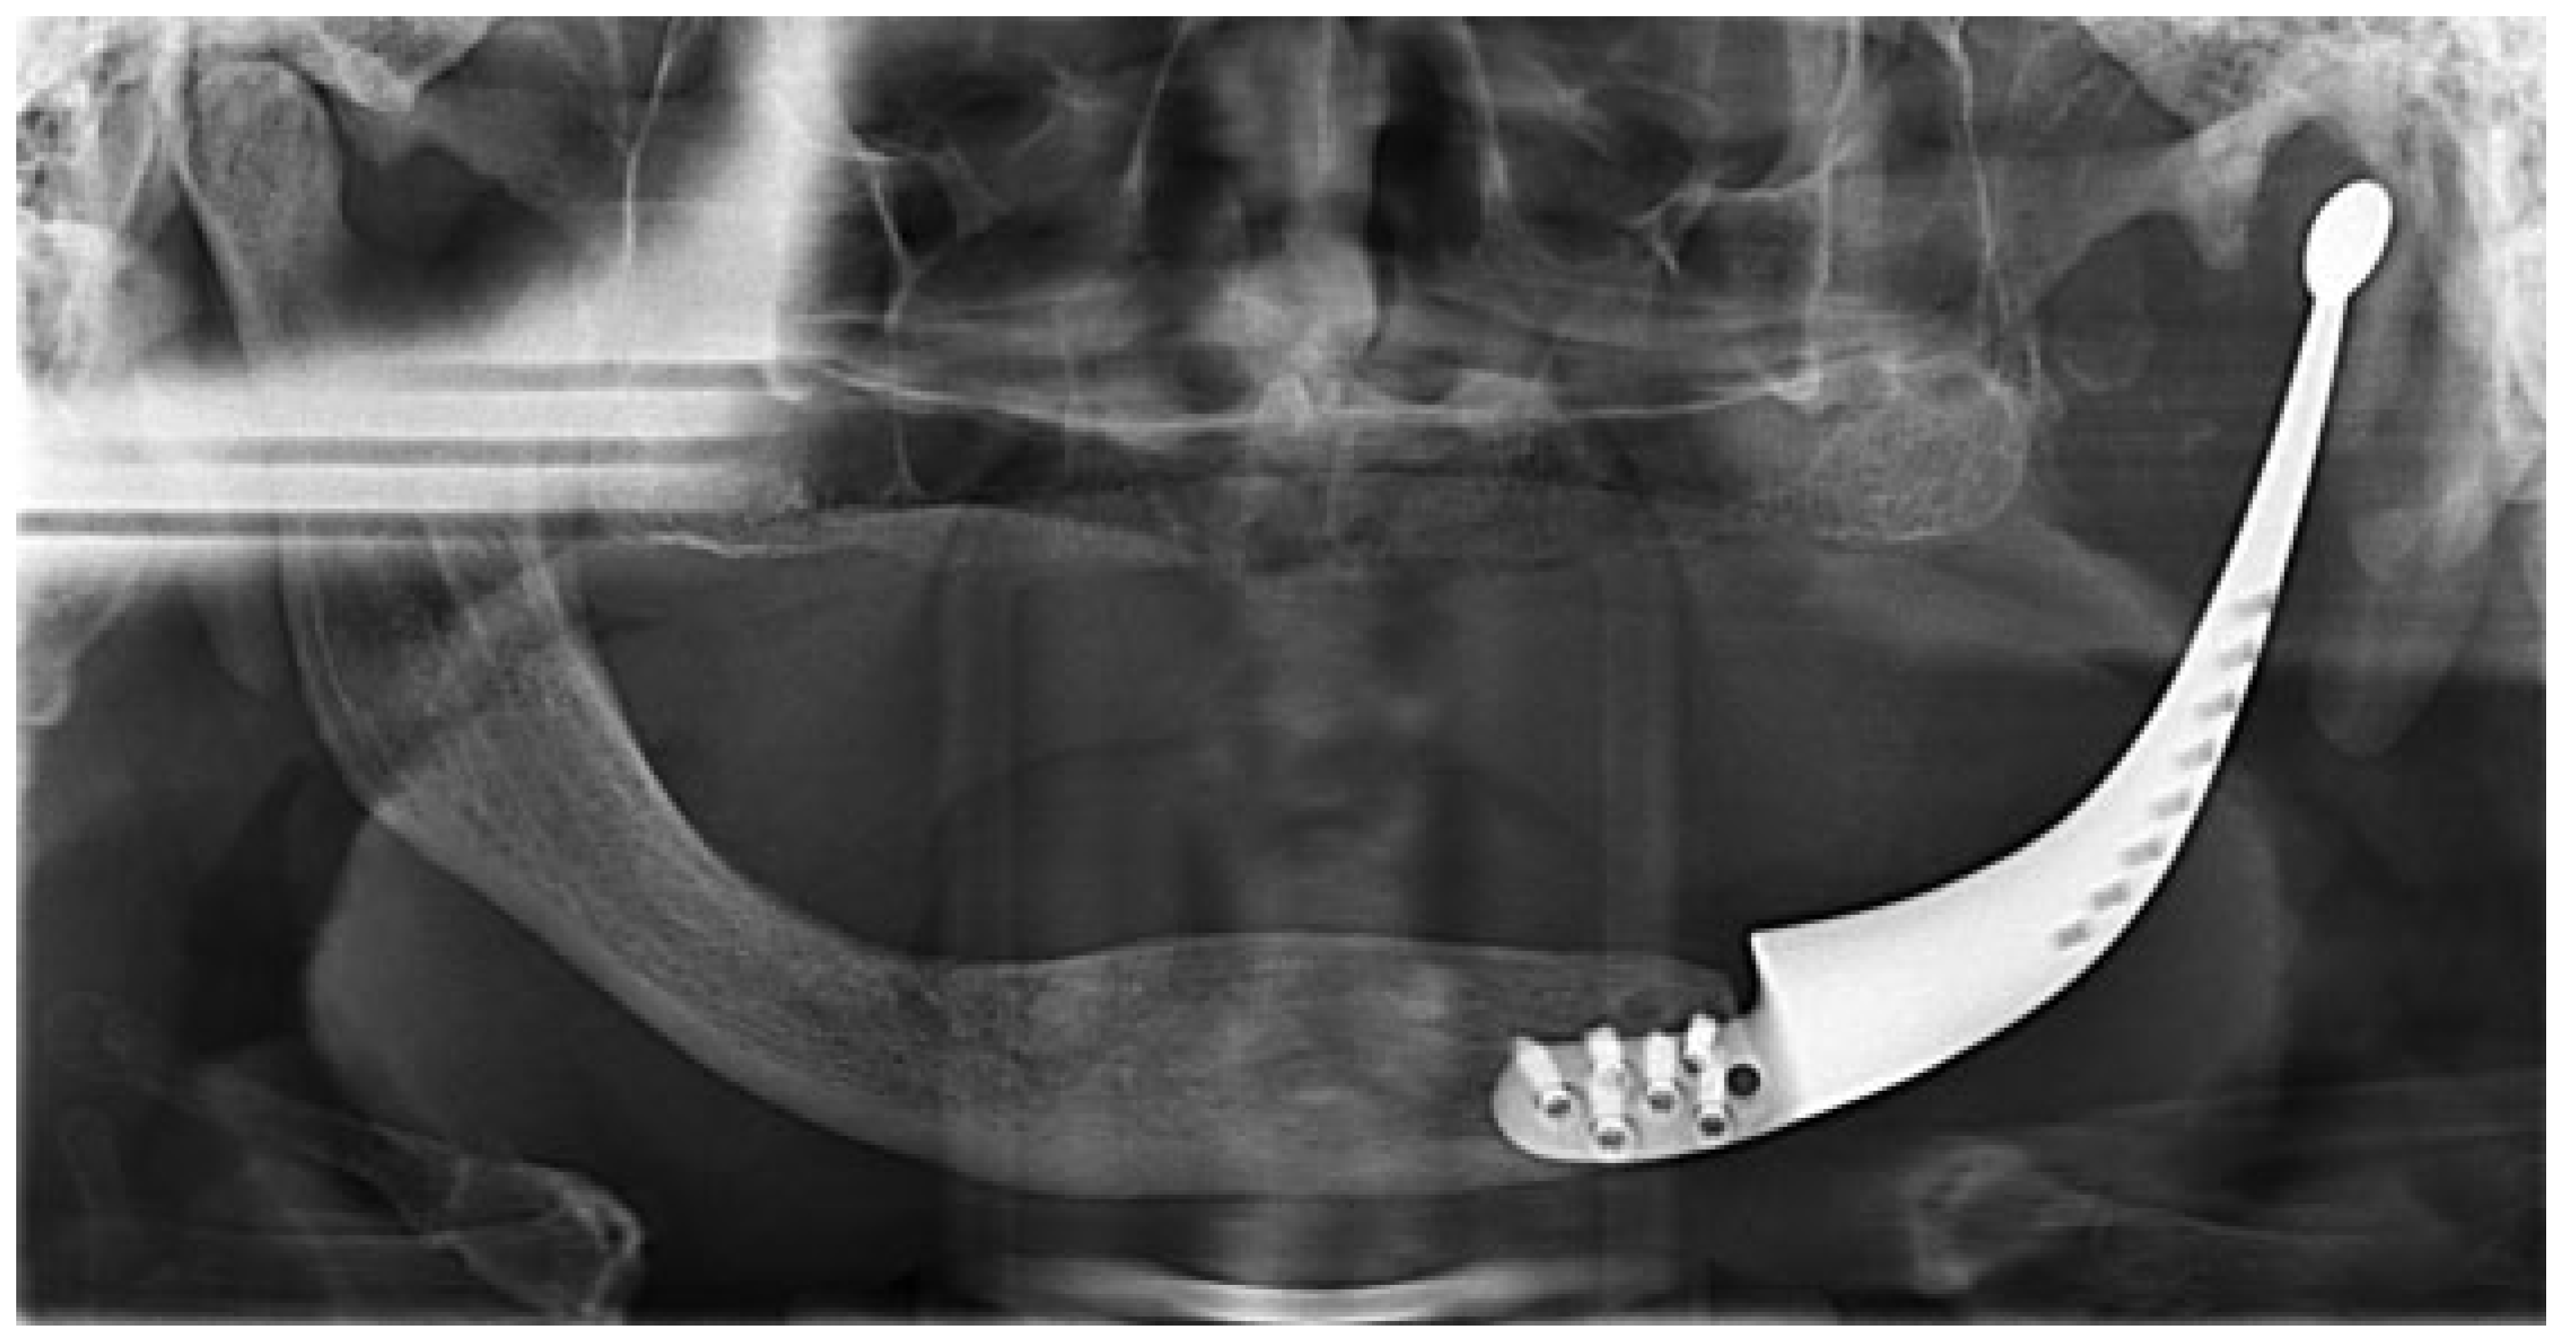

Mandibular Reconstruction Using a Custom-Made Titanium Prosthesis: A Case Report on the Use of Virtual Surgical Planning and Computer-Aided Design/Computer-Aided Manufacturing

:Case Presentation

Design Sequence

Surgical Sequence